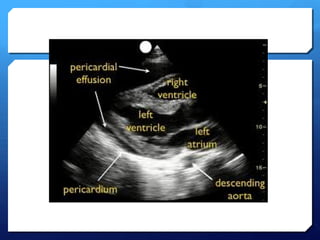

PericardialTamponade

 Remember tamponade is a clinical diagnosis based on

patient’s haemodynamics and clinical picture.

 Ultrasound may demonstrate early warning signs of

tamponade before the patient becomes haemodynamically

unstable.

 Haemodynamic effects

 Its PRESSURE NOT SIZE THAT COUNTS!

 Rate of formation affects pressure-volume relationship and

is therefore more important than volume of fluid.

Tamponade using ultrasound

 A moderate-large effusion.

 Right atrial collapse

 Atrial contraction normal in atrial systole

 Collapse throughout diastole or inversion is abnormal.

 RV collapse during diastole when meant to be filling

(‘scalloping’ seen)

 Whats seen in the IVC…